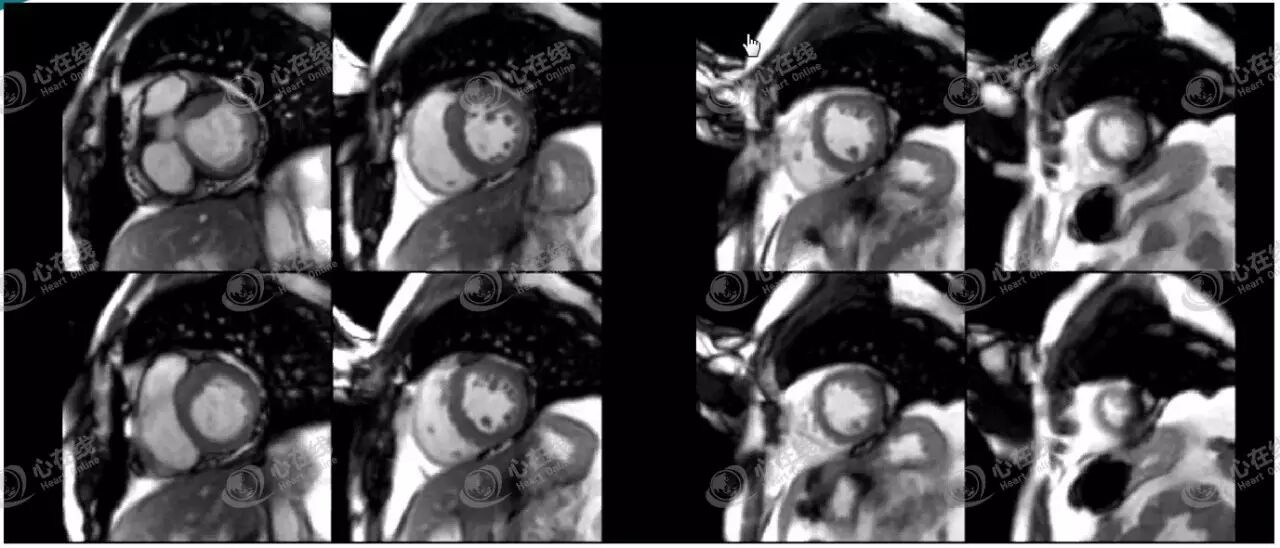

4、功能学检查

1)长轴功能检查。图3为4个重要的评估心脏功能的长轴平面。

图3

2)左室短轴电影(图4)是评估心脏功能的基本平面。利用心脏电影图像,可通过后处理工作站获得心脏整体及节段的功能参数。

图4